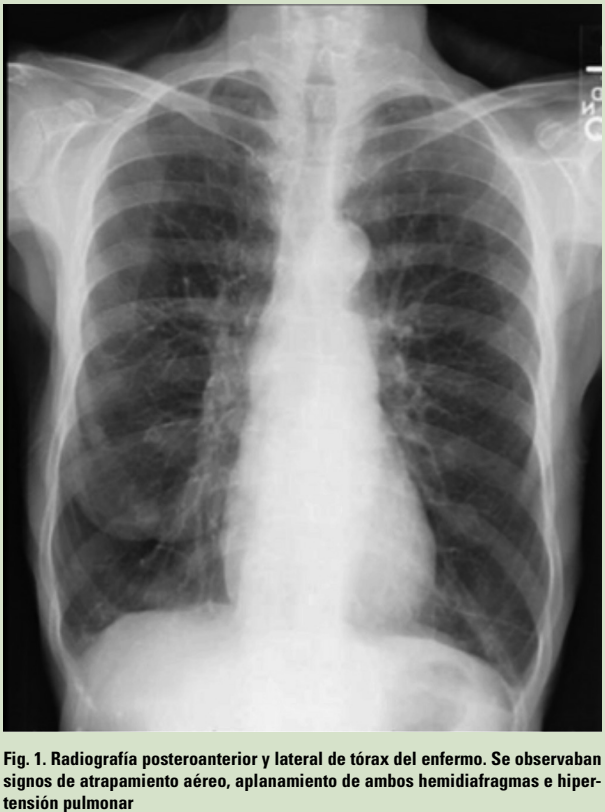

- En la exploración física se observaba un paciente delgado, con IMC 20 kg/m2, sin apenas panículo adiposo, con algunos signos de cianosis en piel y mucosas. La auscultación pulmonar revelaba un murmullo vesicular disminuido en ambos campos pulmonares y la frecuencia respiratoria era de 22 respiraciones por minuto; la auscultación cardíaca era rítmica y sin soplos, con una frecuencia cardíaca de 86 latidos por minuto. La tensión arterial era de 135/78 mm Hg y la saturación de oxígeno medida por pulsioximetría del 91%. El paciente no tenía acropaquias y el resto de la exploración física no mostraba alteraciones significativas.